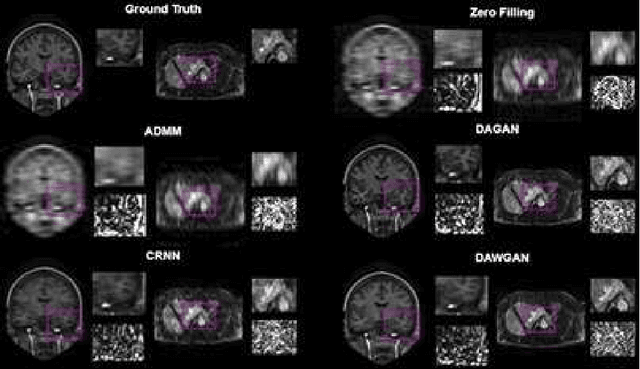

Abstract:The performance of traditional compressive sensing-based MRI (CS-MRI) reconstruction is affected by its slow iterative procedure and noise-induced artefacts. Although many deep learning-based CS-MRI methods have been proposed to mitigate the problems of traditional methods, they have not been able to achieve more robust results at higher acceleration factors. Most of the deep learning-based CS-MRI methods still can not fully mine the information from the k-space, which leads to unsatisfactory results in the MRI reconstruction. In this study, we propose a new deep learning-based CS-MRI reconstruction method to fully utilise the relationship among sequential MRI slices by coupling Wasserstein Generative Adversarial Networks (WGAN) with Recurrent Neural Networks. Further development of an attentive unit enables our model to reconstruct more accurate anatomical structures for the MRI data. By experimenting on different MRI datasets, we have demonstrated that our method can not only achieve better results compared to the state-of-the-arts but can also effectively reduce residual noise generated during the reconstruction process.